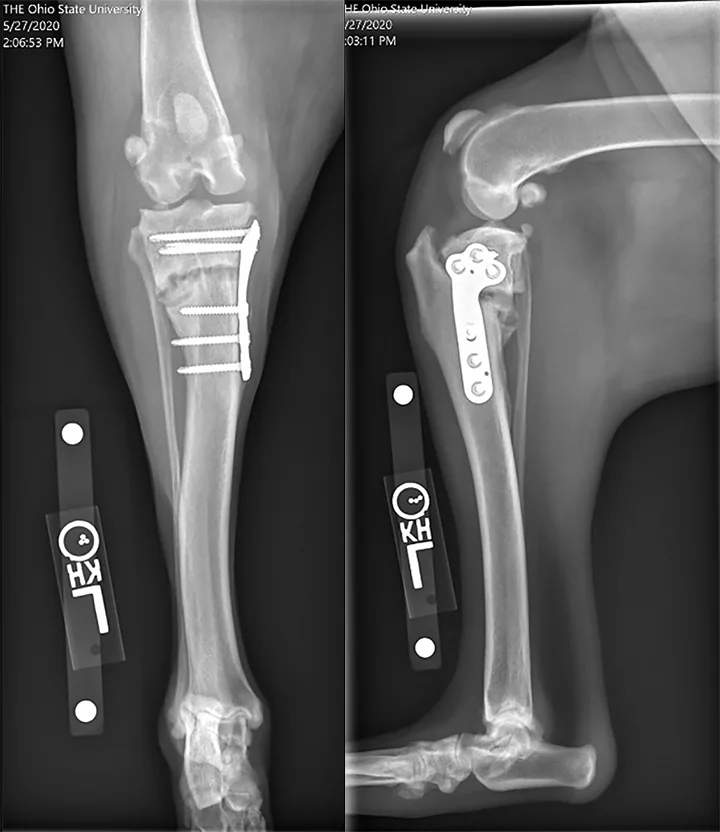

Figure 2

Radiographs from an 8-year-old spayed Rottweiler that underwent TPLO and was diagnosed with a superficial SSI 2 weeks postoperatively at another hospital. The SSI was treated with a 10-day course of antibiotics. The dog was presented to The Ohio State University Veterinary Hospital 6 weeks after surgery for recurrent lameness; the incision was healed, but osteomyelitis was confirmed on radiographs and fine-needle aspirate and cytology. Culture-based antibiotics were prescribed, but the infection did not resolve, the lameness was persistent, and the osteotomy became a nonunion. The patient was euthanized after developing a T3-L3 myelopathy suspected to be related to systemic infection.